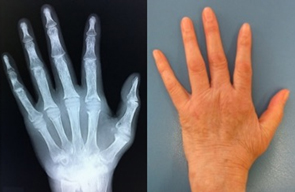

人工手指関節手術前 -

手術後 -

リウマチによる手・肘の変形に対する治療は一般的に難易度が高く、また習熟している施設は限られています。当院ではリウマチ手指や肘に対する人工関節手術を積極的に行い、良好な治療成績を得ています。また比較的若年の方で関節面が保たれている場合は可能な限り関節温存手術を行います。当院の担当医はリウマチ指の人工関節手術、人工肘関節手術、人工関節を用いない手指軟部組織形成術や肘関節形成術の経験も豊富です。人工関節は複数の種類がありますが、患者さんの状態に合わせて使い分けています。肩については、変形性関節症のところでも触れている、近年開発された肩の特殊な人工関節(リバース型)が導入されて以降、良好な成績が得られています。